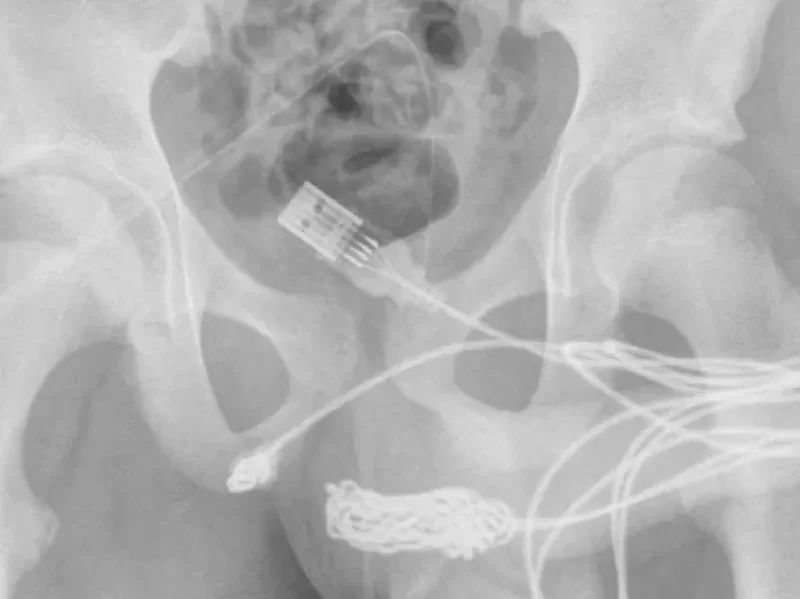

“Se descubrió que los dos puertos distales del cable USB sobresalían del meato uretral externo, mientras que la parte media del cable anudado permanecía dentro de la uretra”, indicaron los médicos en un informe difundido por ScienceDirect.com.

En un primer momento, los expertos buscaron extraer el cable del pene con una varilla de metal. Pero como había una gran cantidad de nudos en el cable, el paciente tuvo que ser operado.

Durante la cirugía para extraer el cable que tenía atrapado el joven en su pene, los médicos realizaron una inserción entre los genitales y el ano. De esa forma, lograron acceder al USB mediante los catéteres que habían colocado.

"Se realizó una incisión penoescrotal longitudinal sobre el cuerpo extraño palpable y se realizó una disección cuidadosa a través de los tejidos más profundos, dividiendo el músculo bulboesponjoso", detallaron los expertos sobre el procedimiento insólito. Allí también destacaron que “ambos extremos del cable se sacaron con éxito a través del meato uretral externo”.